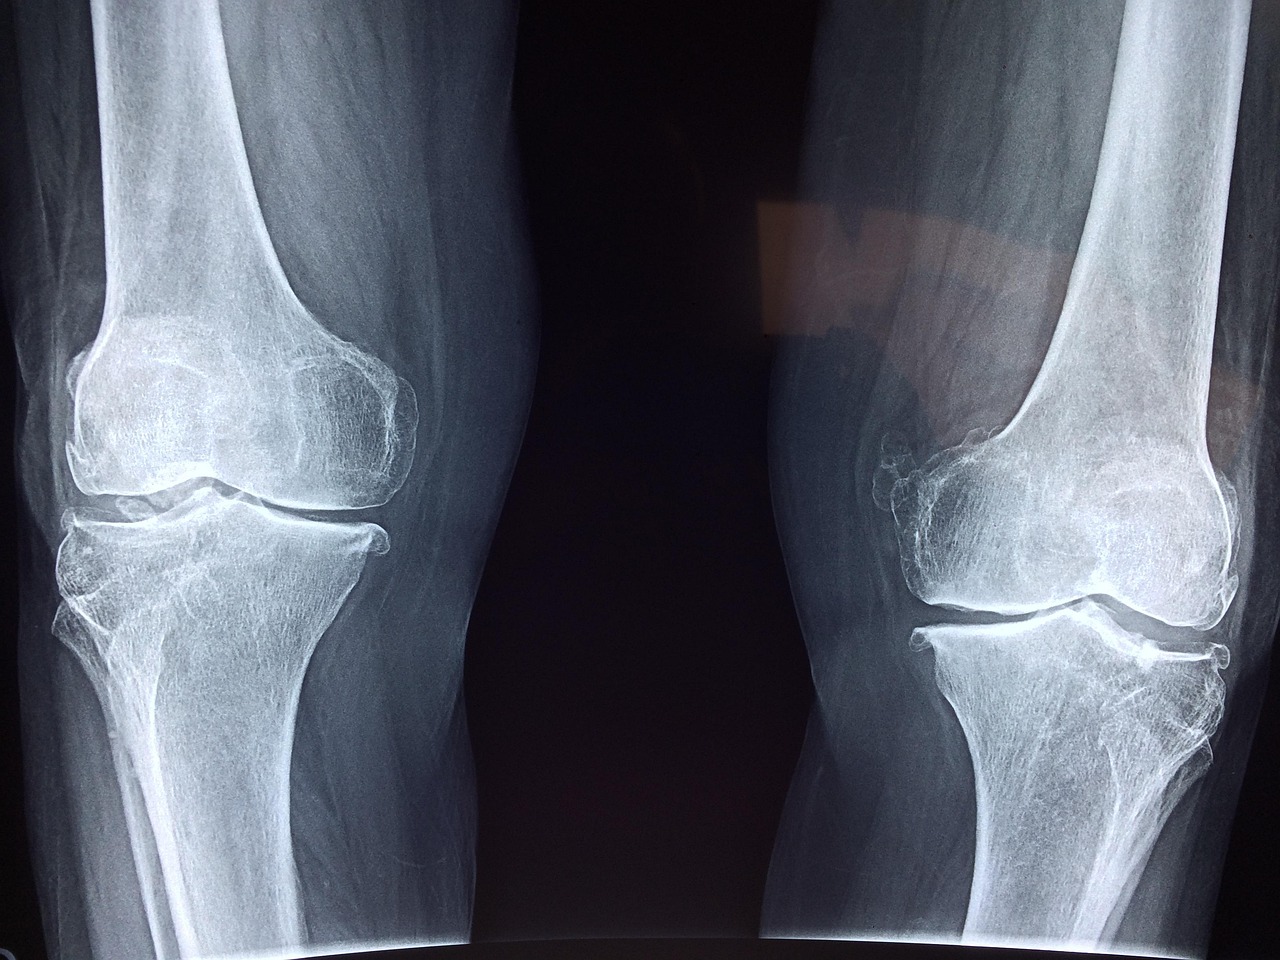

Laboratorijski testi so potrdili, da je “Bone 02” uspešno prestal merila za varnost in učinkovitost. V enem izmed poskusov je bil postopek zaključen v manj kot 180 sekundah ali treh minutah, medtem ko bi konvencionalne metode zdravljenja zahtevale večji rez za vstavitev jeklenih plošč in vijakov. Lepilo je bilo uspešno preizkušeno na več kot 150 pacientih. Zlepljene kosti so pokazale največjo vezno moč več kot 400 funtov, strižno trdnost približno 0,5 MPa in tlačno trdnost okoli 10 MPa, kar poudarja, da ima izdelek potencial za zamenjavo tradicionalnih kovinskih vsadkov. Znanstveniki so navedli, da bi lahko tudi zmanjšalo tveganja za reakcije in okužbe.